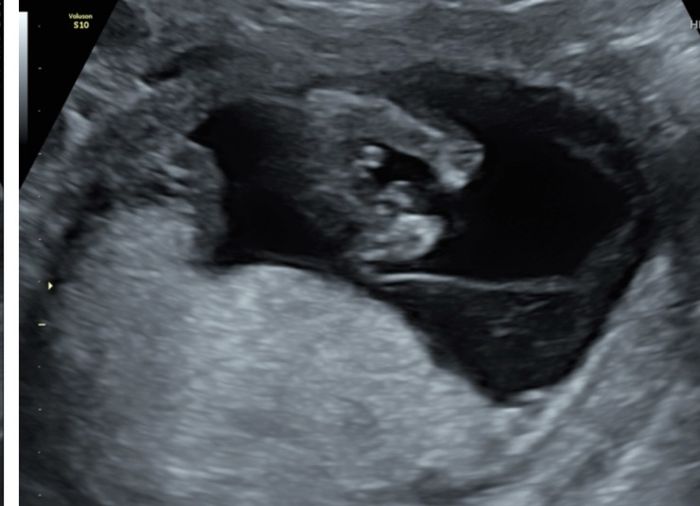

Nub theory, giochiamo un po’

Ciao ragazze, lunedì scorso ho fatto eco genetica a 11+5 ma bebè misurava 12 settimane, ho fatto dna fetale che dovrebbe arrivare questa settimana, ma nel frattempo per...